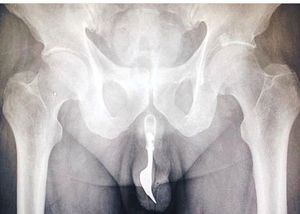

A 70 year old male rush to the hospital after he attempt to achive sexual gratifaction by inserting a 4 inch fork into his male organ... The media reported that he struck utensils into his urethra and sruggled for 12 hour to retrive it prior to the hospital visit..Doctor were able to feel the fork from outside and then clearly see the picture of cuttery in radiographic imaging.. However ones it has been located 'multiple retrieval method' were contempelated with success achive by foreceps traction and coupious lubrication.After the surgery the man was sent home with no long term damage...